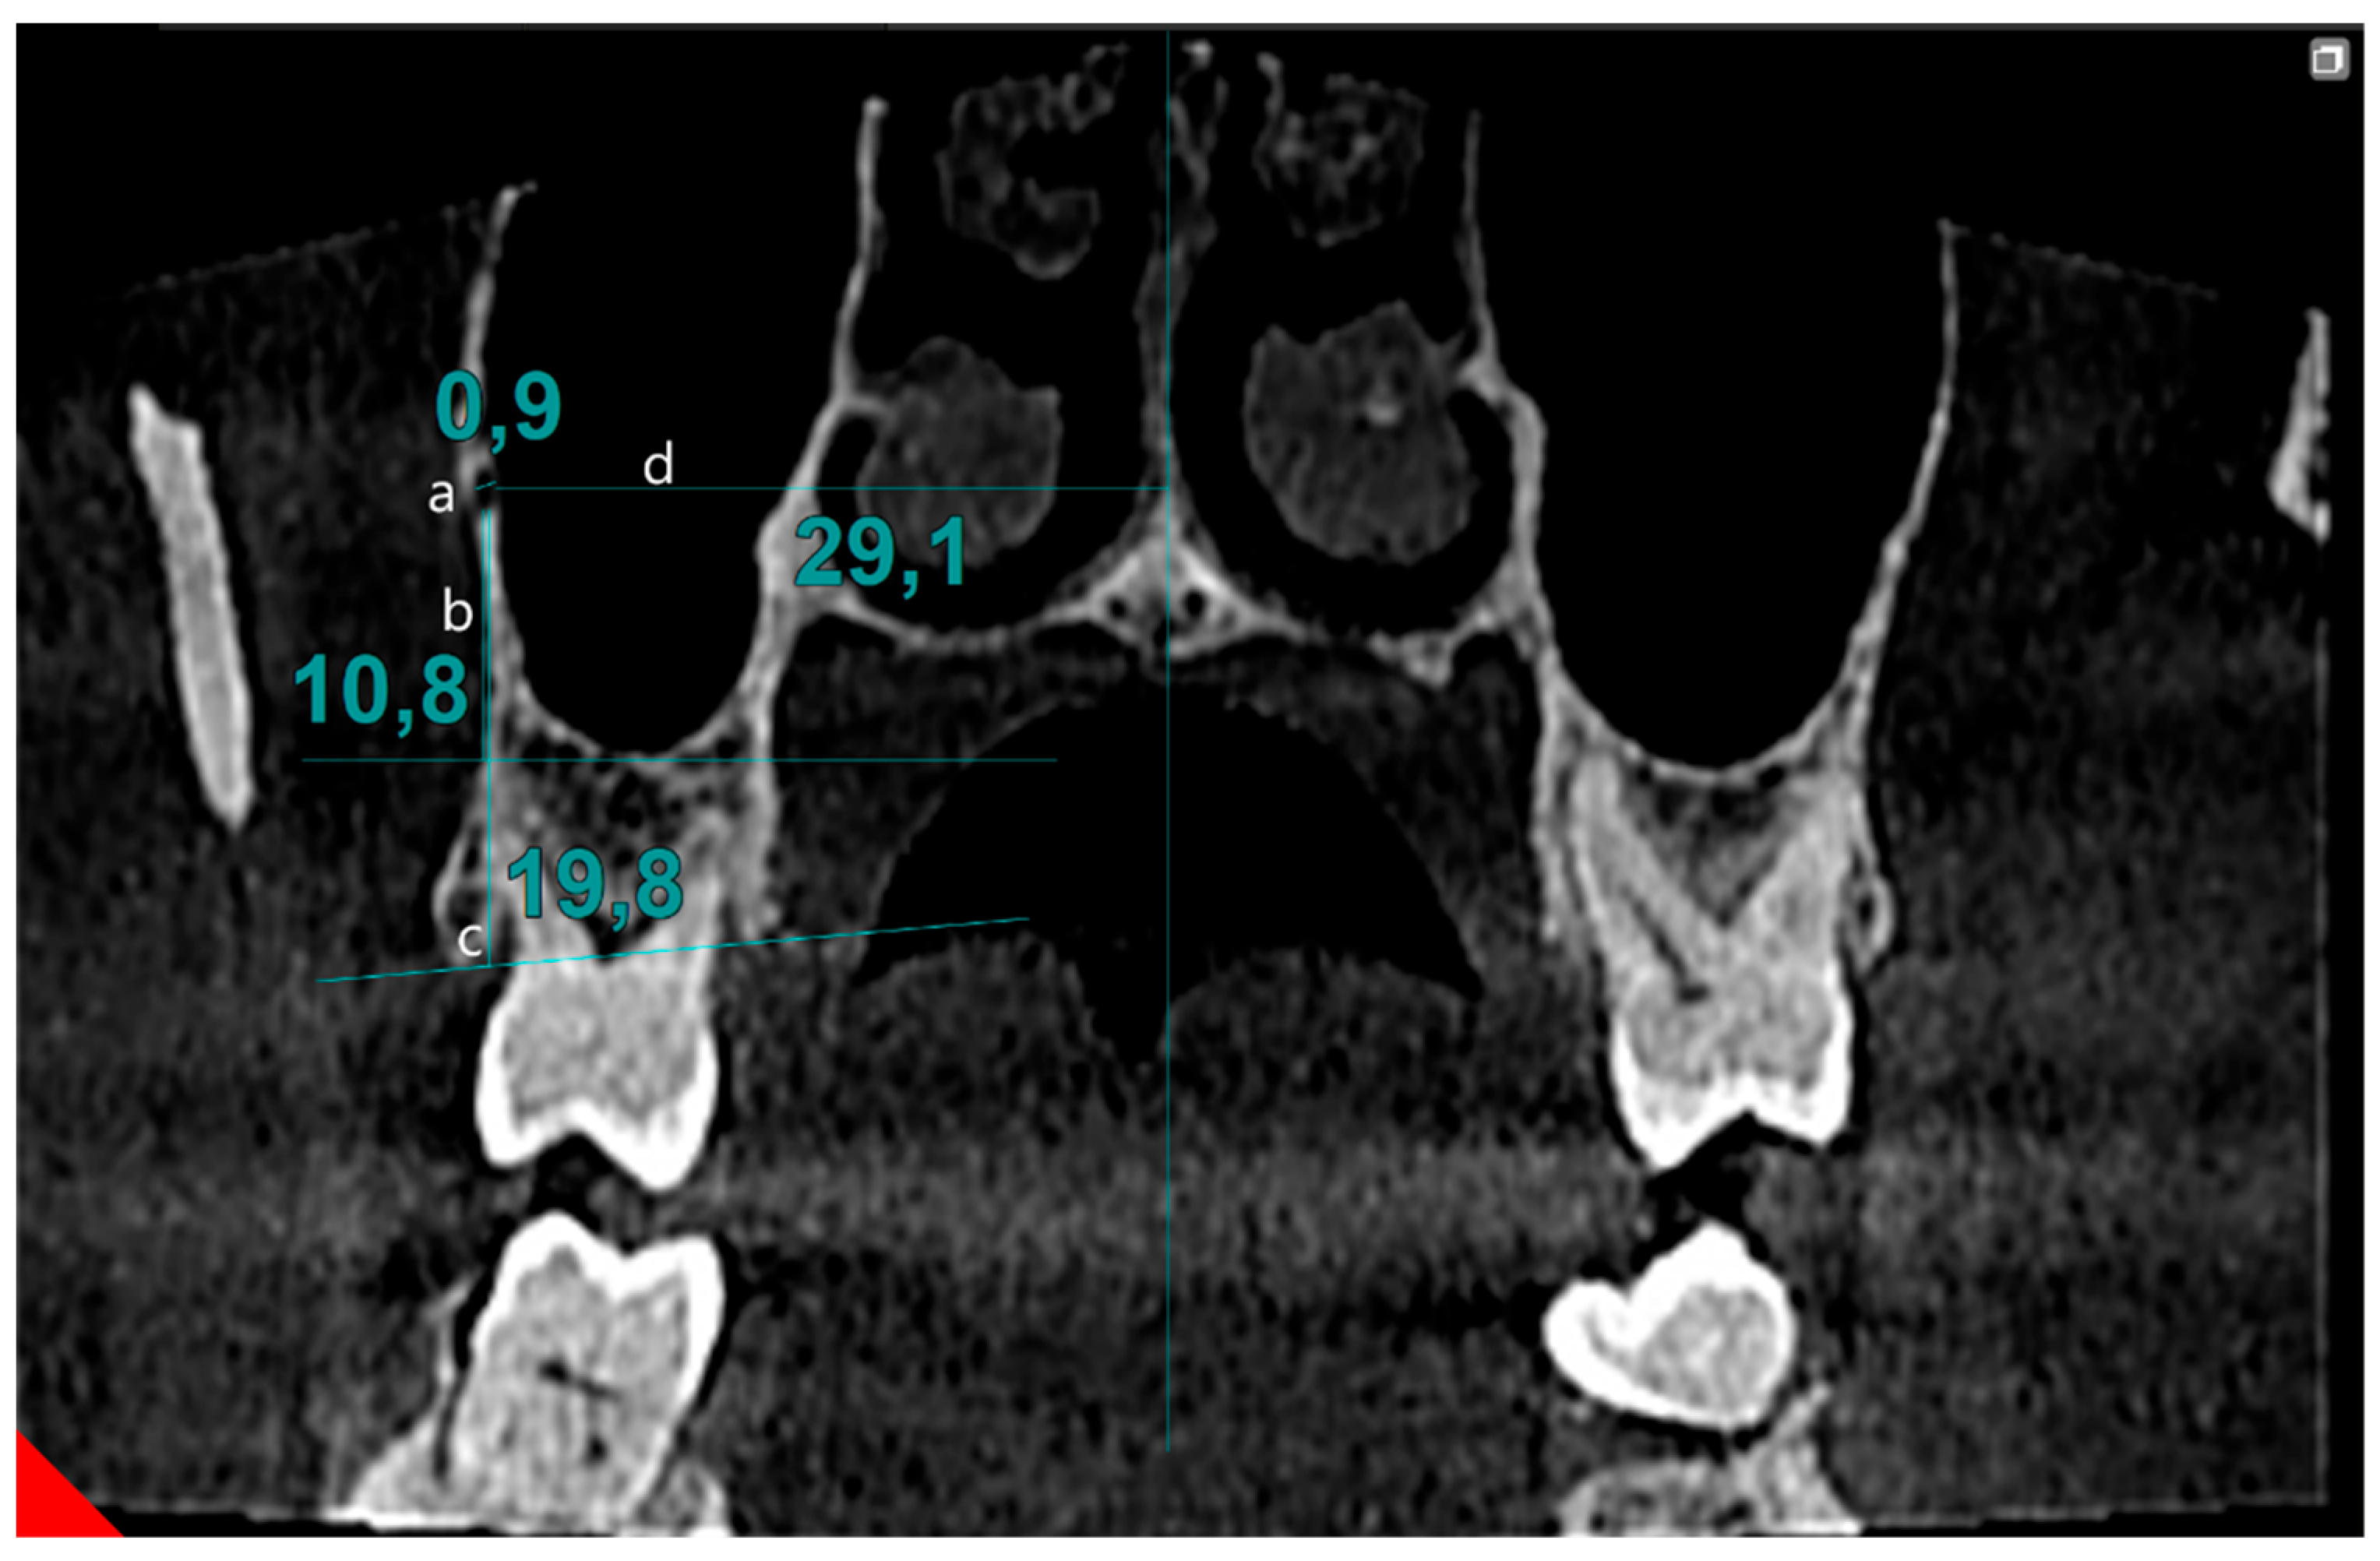

Cone beam computed tomography data were assessed by two observers (M.F. and İ.Y.) on two separate occasions, with a two-week interval between evaluations, to assess inter- and intra-observer variability. Scans were performed in the coronal section, moving from posterior to anterior, to identify the PSAA canal. During the scanning process, if a canal in the lateral wall of the sinus was detected, its image in the transverse section was simultaneously reviewed. Once confirmed, measurements of the canal continued in the coronal section. The localization of the canal was determined based on its position in the bone tissue: extraosseous (outside the bone), intraosseous (within the bone), and intranasal (inside the maxillary sinus). The image was magnified fourfold to determine the canal diameter. The line drawn between the inner surfaces of the cortical bones was defined as the canal’s diameter. The distance to the sinus floor and alveolar crest was measured from the canal. Also, the distance between the nasal septum and the central point of the canal was recorded (Figure 1).

Figure 1.

Evaluation of PSAA parameters: (a) diameter of PSAA, (b) distance of PSAA from sinus floor, (c) distance of PSAA from alveolar crest, (d) distance of PSAA from midline.